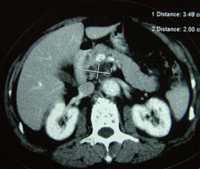

黃先生告訴記者:2004年7月初,他大便次數增多,腹部隱隱不適,去江門市人民醫院檢查,做B超和CT,發現胰腺腫癌。突然的打擊幾乎讓他精神崩潰。黃先生的太太是護士,對胰腺癌的嚴重性早有所聞。有醫生勸黃先生接受手術,但全家反對,一方面黃先生年事已高,另一方面他們了解胰腺癌能切除者微乎其微。一位鄰居告訴他們:廣州復大腫瘤醫院有不開刀的冷凍治療,對肝癌、肺癌等許多腫瘤有良好效果。7月14日,夫妻倆帶著簡單的行李,直奔廣州,當日住進復大腫瘤醫院。牛立誌博士等醫務人員給黃先生作了詳細檢查,作了腫瘤活檢,確診為胰腺囊腺癌。7月16日,黃先生接受了冷凍加125-碘粒子植入治療。醫生在CT引導下,作腹部穿刺,不開刀,將細針直接插入胰腺腫瘤內,先冷凍,再植入125碘粒子20粒。第二天,黃先生下地行走;第三天,恢復正常飲食;第八天,出院回家。三年來,除腿關節有點老年退化性變性外,他生活完全正常,無疼痛,食欲好,睡得香,每天散步半小時。CT復查顯示:胰內腫瘤消失。

黃先生胰腺癌治療前後CT:A 治療前,B 治療後3個月,C 治療後12個月